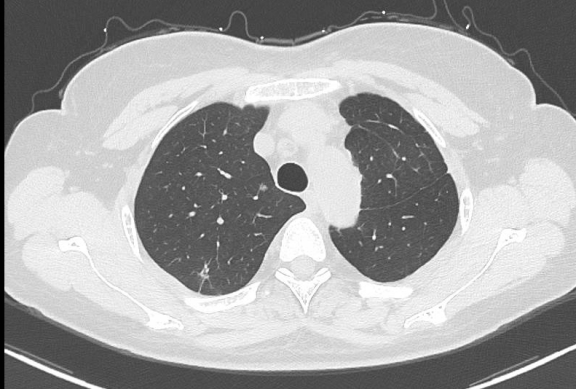

近日,广元市第一人民医院心胸血管外科团队勇闯高危手术“禁区”,成功为一位特殊的肺癌患者实施了Tubeless(无气管插管)自主呼吸麻醉下的单孔胸腔镜右肺上叶肿瘤切除术,最大程度减轻该患者双肺结节术后肺功能受损。该手术的成功开展,标志着医院胸外科微创技术及加速康复外科理念的应用迈上了新台阶,为心肺功能差、无法耐受传统单肺通气的复杂肺癌患者开辟了安全、精准、高效的手术新路径。

患者左肺上下叶均曾罹患肿瘤并接受过手术治疗,此次右肺上叶新发肿瘤,为其治疗带来了巨大挑战:

1. 肺功能储备严重受损:左肺已部分切除,肺功能基础差;

2. 无法耐受传统麻醉:传统的胸腔镜手术需要双腔气管插管进行单肺通气,但该患者因仅存的右肺也需要接受手术,且身体条件无法耐受单肺通气,这使得常规手术方案无法实施。

若放弃手术,患者将失去根治性治疗的机会。面对如此棘手的病情,心胸血管外科团队毅然决定迎难而上,经过多学科团队(MDT)的精密评估和充分讨论,最终为患者“量身定制”了国内领先的 Tubeless单孔胸腔镜手术方案。